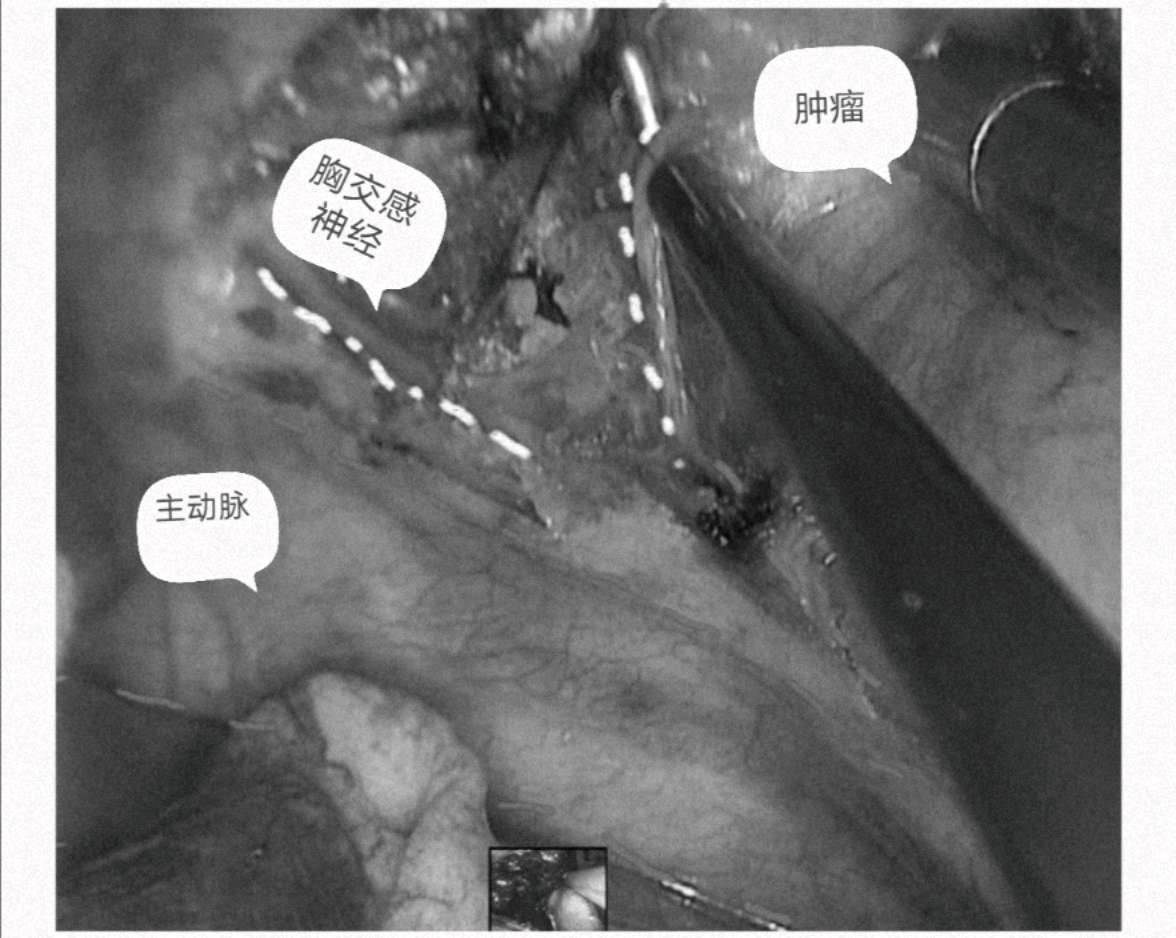

喔哦!这是什么?见下图:后纵隔脊柱旁巨大占位,横跨6个椎体,长达12cm。患者女性,22岁,单位体检CT发现(大部分由于心脏,纵隔器官的遮挡需胸部CT检查才能发现),运用我们的微创单孔3cm切口胸腔镜技术完美切除,术后4天顺利出院。术后诊断为罕见的胸交感节神经细胞瘤,此瘤的特点虽大部分是良性,但喜欢往缝隙里长,比如椎间孔,有报道以截瘫或神经症状而就诊的,本例肿瘤边有主动脉大血管,底有肋间神经血管,椎间孔,脊髓,任何一处都损伤不得。

3cm切口切除12cm的大肿瘤。胸腔镜微创外科的魅力。